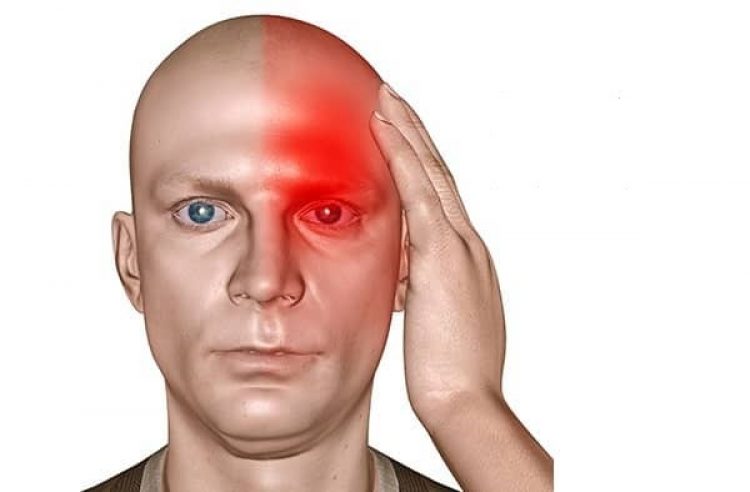

Některé bolesti hlavy mohou být život ohrožující, jiné, ač nejsou tak fatální, dokážou brát roky života. Bolestí hlavy existuje mnoho druhů a někdy může být těžké se v nich vyznat.

Bolesti hlavy se dle mezinárodně uznávané klasifikace rozdělují na primární a sekundární. Sekundární jsou projevem jiných onemocnění, a to od poměrně nezávažných, jako jsou například chřipka či zánět nosních dutin, až po závažné a život ohrožující, jakými mohou být nádor mozku či zánět mozkových blan.

Primární bolesti hlavy jsou naopak onemocněním samy o sobě. Řadí se mezi ně migréna, tenzní bolesti hlavy a cluster headache.

„Primární bolesti hlavy, jako je migréna, nás neohrožují na životě, a proto mají někdy lidé tendenci je zlehčovat, a to i přesto, že ze všech bolestí hlavy způsobuje např. migréna nejvyšší míru dočasné nemohoucnosti pacienta.

Je charakterizována opakovanými záchvaty bolestí hlavy středně silné až velmi silné intenzity doplněné o doprovodné příznaky, jako je například nevolnost, zvracení, světloplachost a extrémní únava. Dle klasifikace je migréna dělena na migrénu s aurou a migrénu bez aury.

Migrénu s aurou zažívá okolo 20 % pacientů. Samotná aura předchází vlastní migrenické bolesti hlavy a běžně se může projevovat dočasnou poruchou zraku a zorného pole, jako jsou záblesky a vidění vlnovek nebo drobných předmětů.